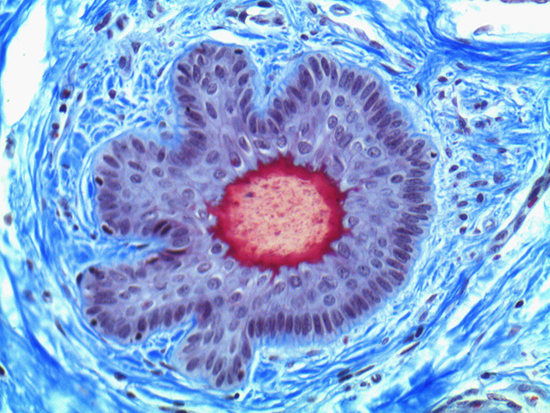

Figure 3: Brightfield Image of Dermal Tissue filtered with Green

When comparing Figure 3 with Figure 4, there is once again a significant visual difference. The most obvious feature is the change in color from green to red due to a different hardcoated filter being positioned in the optical path. The less obvious difference is the varying contrast levels caused by the filters at specific regions of the dermal tissue. For example, Figure 3 exhibits a distinct ring at the central region of the cell with additional matter within. In Figure 4, the ring is extremely faint and the internal matter is not visible. With that said, the cell and surrounding dense materials are more evident in Figure 3, whereas the muscle fibers and collagen are more pronounced in Figure 4.